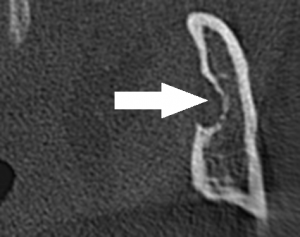

静止性骨空洞は下顎骨の内側(舌側)が陥没し、そこに唾液腺組織や脂肪組織が入り込んだ状態で、その様子はCT画像で鮮明に観察できます。通常、静止性骨空洞は治療の必要がありませんが、徐々に空洞が大きくなる場合は手術により中に入り込んだ唾液腺組織や脂肪組織を取り除く必要があります。